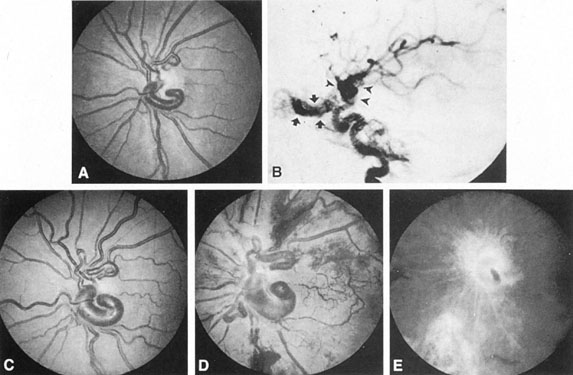

Fig. 2. Terson's syndrome. Multiple preretinal hemorrhages accompanying subarachnoid bleeding.

Fig. 7. Supratentorial arteriovenous malformation in a 28-year-old woman with a history of focal motor seizures for many years and a recent subarachnoid hemorrhage. A: Lateral projection carotid arteriogram demonstrating a huge deep hemispheral arteriovenous malformation. B: Frontal projection. C: Fundus photograph showing anomalous tortuous vasculature in each eye. No retinal arteriovenous shunt was detectable.

Fig. 11. Embolization of middle cerebral vessels that supply occipital lobe arteriovenous malformation (AVM). The patient had a subarachnoid and intraparenchymal hemorrhage that produced a left homonymous field defect. A: Right carotid arteriogram demonstrates contribution via posterior communicating artery to a right occipital lobe AVM. B: Vertebral injection. The arrow points to the enlarged right posterior cerebral artery that is a major feeder of the AVM. C: Right carotid arteriogram during glue embolization procedure. The arrow points to a catheter as it traverses the segment seen in (B). The catheter was advanced via the internal carotid artery but is positioned far posteriorly. D: Upper branches to the AVM now are occluded, with residual low-flow vascularization via the middle cerebral artery. E: Skull film showing radiopaque glue within the AVM and blood vessels previously supplying it. The patient had a persistent visual field defect but greatly reduced headache and no persistence of subjective bruit. (Courtesy of Dr. Joseph Horton.)